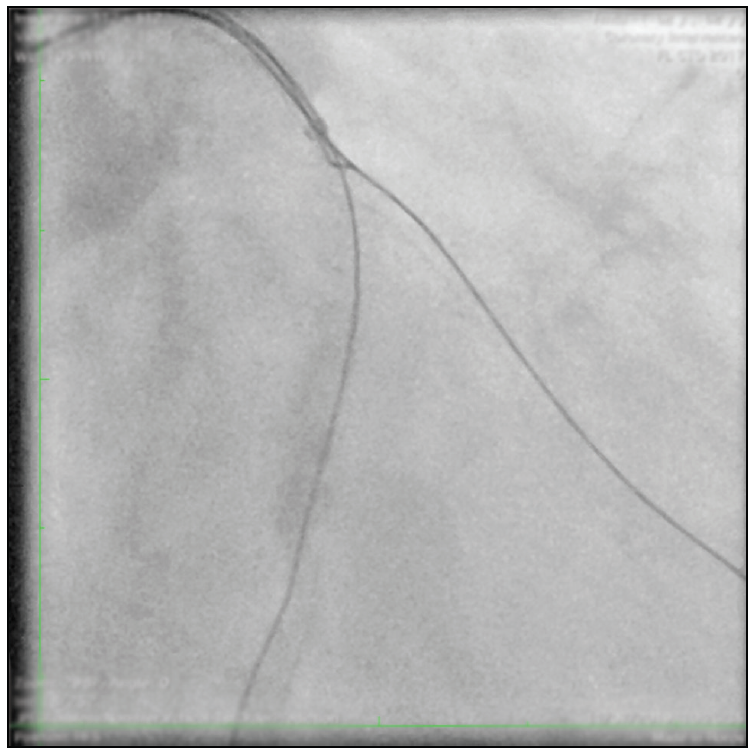

APPROACH of the moderator

The procedure was continued by gaining support with a 6-F Guidezilla II extension. Predilations were alternatively done, in both branches, with semicompliant balloons (a 1.25- X 15-mm Tazuna [Terumo Europe] at 20 atm and then a 2.5- X 15-mm Tazuna at 18 atm) (Figure 3). The culotte technique was chosen considering the similar size of both branches and the presence of severe calcium. A Coroflex ISAR NEO stent (2.75 X 19 mm; B. Braun Melsungen AG) was advanced and implanted at 14 atm at the LCX across the OM1 ostium. Proximal optimization therapy was performed with a 3.5- X 8-mm NC Emerge balloon (Boston Scientific Corporation) at 12 atm. After regaining the OM1 access with a Sion guidewire (Asahi Intecc USA, Inc.), the stent struts were opened to the OM1 with a 2.5- X 15-mm Tazuna balloon at 10 atm (Figure 4) and a 3- X 32-mm Coroflex ISAR NEO stent was implanted at the OM1 (Figure 5).